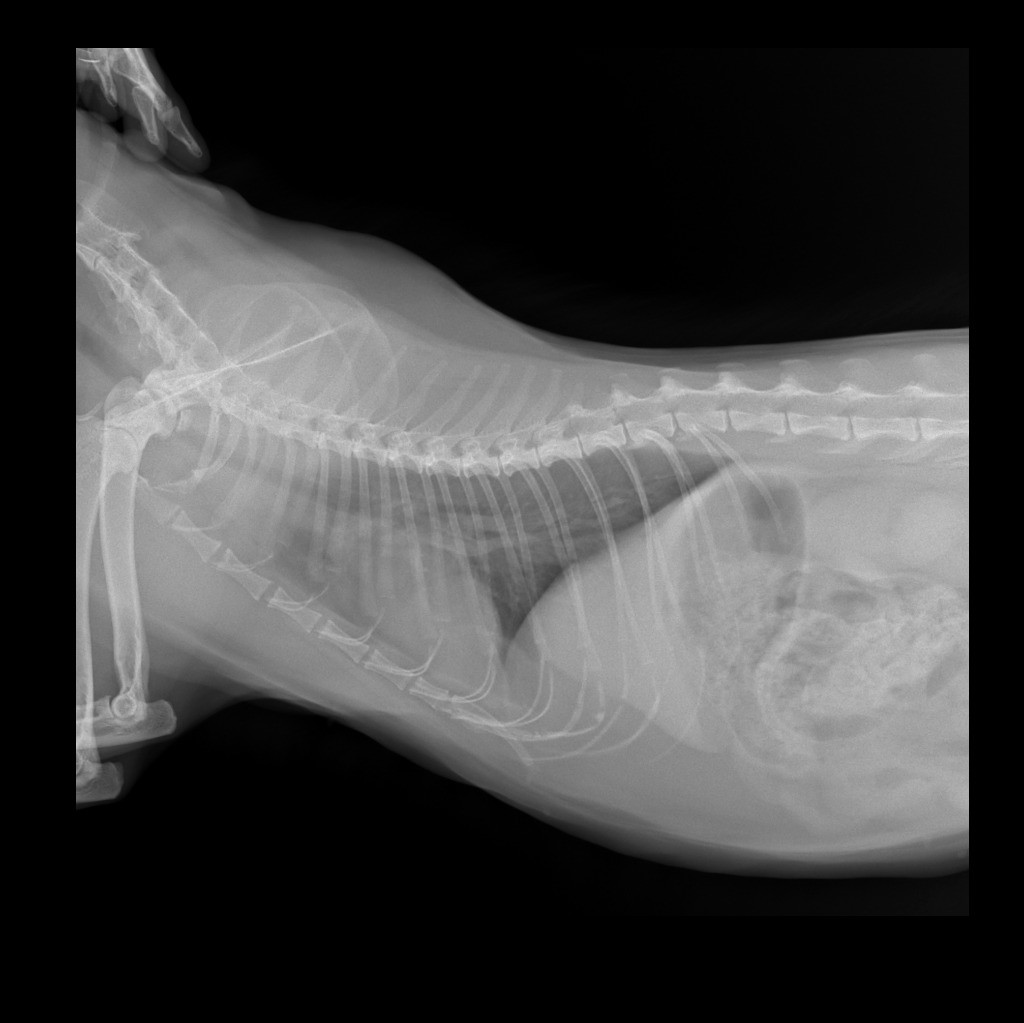

здравствуйте! Кошка начала кашлять, опустив вниз голову и высунув язык трубочкой, шерсть не выходит, длительность приступа около 30сек. Сделали рентген легких по рекомендации ветеринара, сердце проверили, в норме. Посмотрите пожалуйста рентген снимки, что по ним можно сказать?

Здравствуйте. На рентгенограммах видим усиление бронхиального рисунка, что может указывать на хронический бронхит или начало бронхиальной астмы у кошки. Учитывая характер кашля (с вытянутой шеей и языком), вероятна бронхоспазматическая реакция. Рекомендую провести бронхоскопию или хотя бы анализ мокроты (если получится получить), а также рассмотреть ингаляционное лечение (с альбутеролом или флутиказоном).

Здравствуйте. На снимках нет явных признаков новообразований или отека легких, сердце действительно в пределах нормы. Однако в дорсовентральной проекции отмечается небольшое затемнение в каудальных отделах легких это может быть связано с воспалением или астматическим компонентом. Кашель может быть реакцией на аллерген или накопление слизи. Обратитесь к ветеринарному аллергологу или продолжите диагностику по плану. Если приступы станут чаще тогда стоит срочно обсудить назначение пробного курса бронхолитиков.